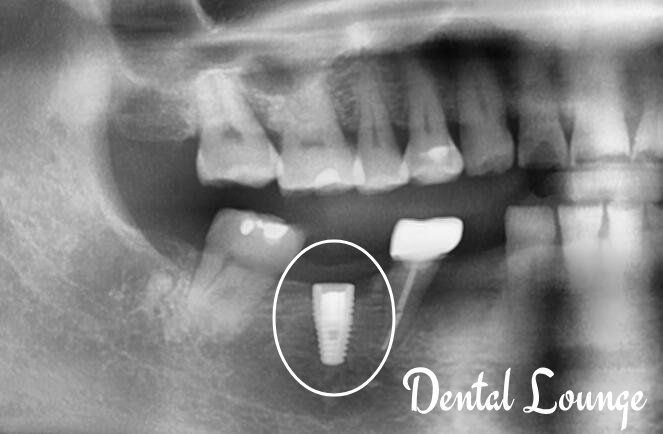

Immediate Implant Placement at #45 Following Extraction of Cracked Tooth

Patient presented with a deeply cracked lower premolar (#45) causing pain on biting. Following clinical and CBCT assessment, the tooth was atraumatically extracted and immediately replaced with a dental implant and bone graft for long-term restoration and function.